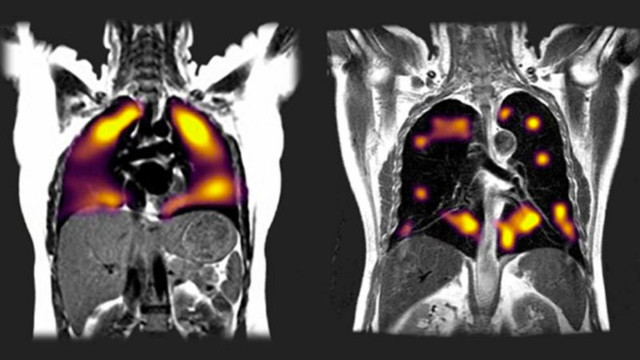

Solda sağlıklı akciğer, sağda ise Covid nedeniyle hasarlanmış akciğer görülüyor. Sağdaki daha büyük siyah bölgeler, oksijenin yeterince kana aktarılamadığını gösteriyor.

Tarama sırasında ksenon gazını içine çeken hastalardan nefes darlığı çektiğini söyleyen 8'inde, akciğer hasarının işaretleri görüldü.

Uzmanlar, hastalardaki akciğer hasarının, geleneksel tarama yöntemleriyle tespit edilemediğine de işaret etti.